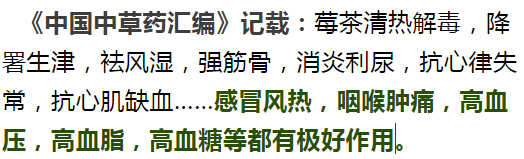

出发之前,我查了很多土家莓茶的资料,做了充分准备——